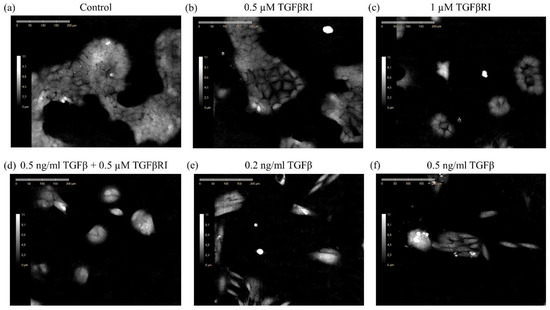

3.1. Monitoring of Epithelial to Mesenchymal Transition Using DHC